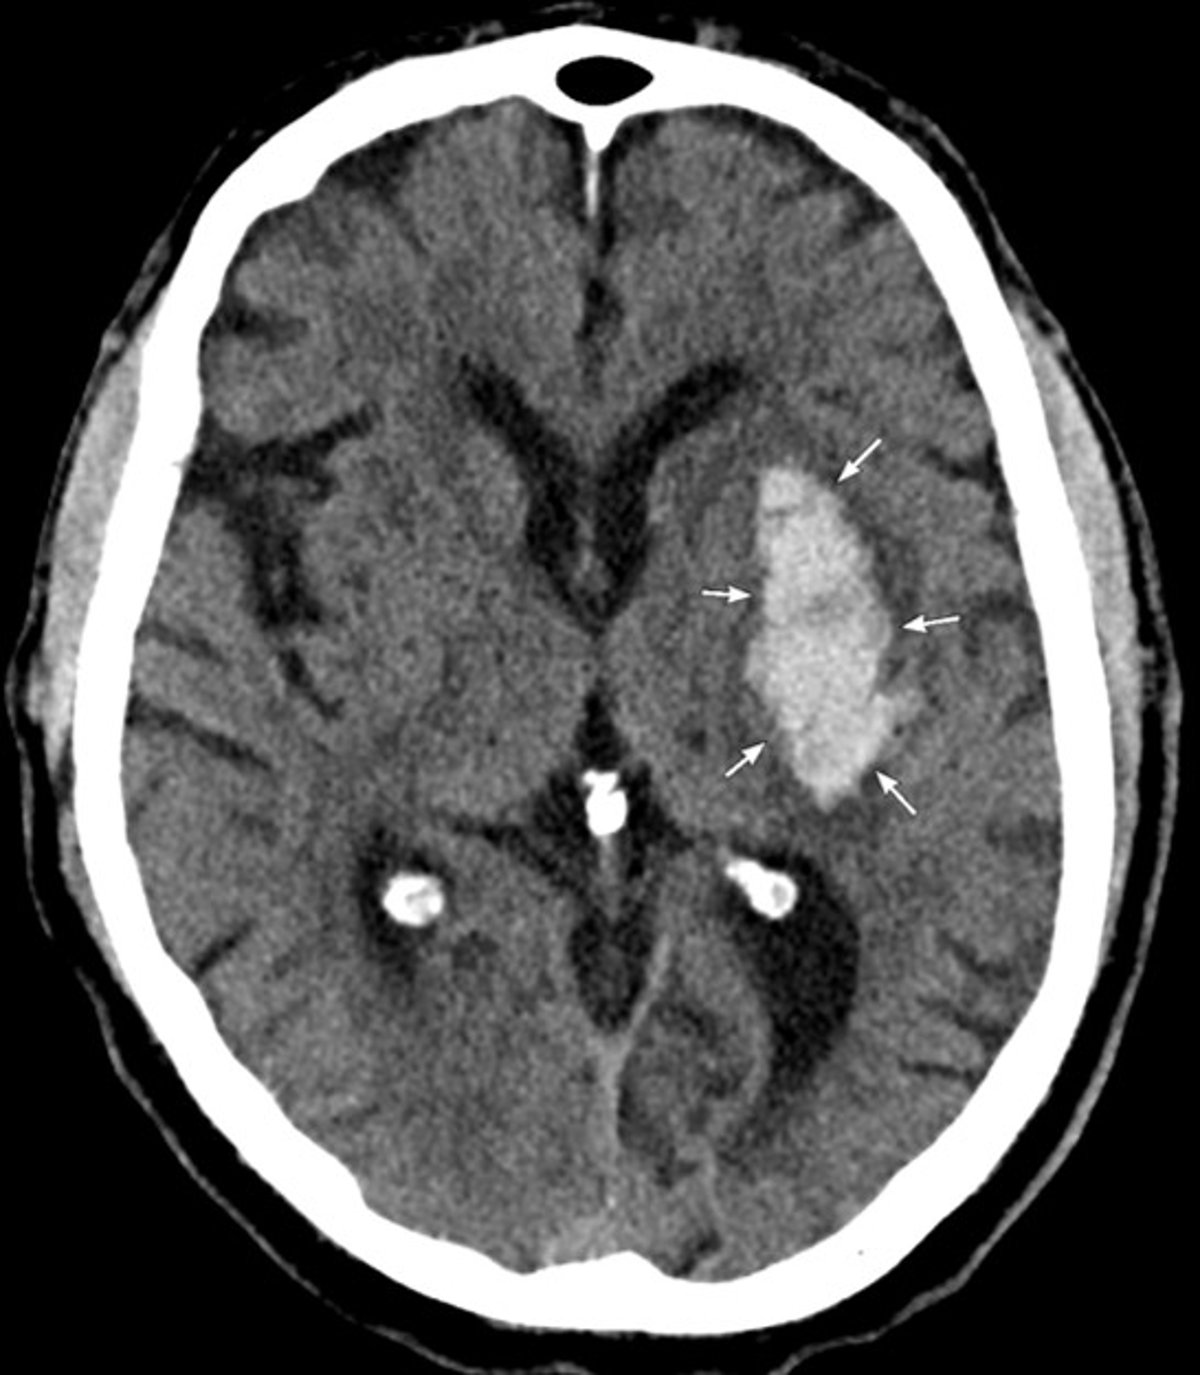

CT cho thấy xuất huyết cấp tính ở hạch nền bên trái phù hợp với xuất huyết nội sọ do tăng huyết áp.

Hình ảnh do bác sĩ Mustafa Mafraji cung cấp.